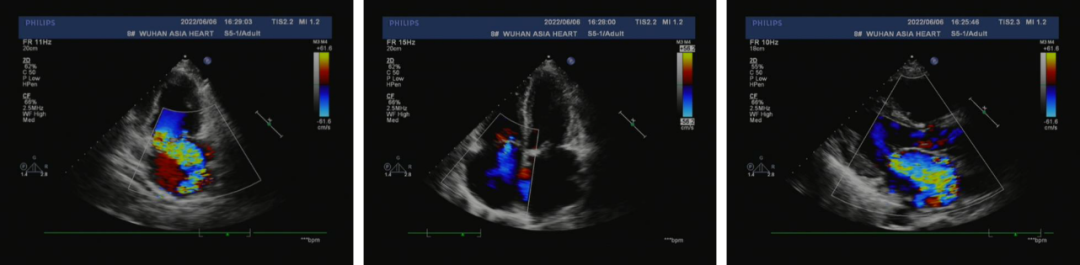

患者男,54岁,主诉活动时胸闷气喘2月余,休息后逐渐缓解,伴有恶心、间断双下肢水肿,并有夜间阵发性呼吸困难。入院诊断为二尖瓣关闭不全,心房颤动,心功能III级;前降支病变,左前降支中段心肌桥。

经整体评估后,拟行二尖瓣置换、冠脉搭桥及房颤消融手术。由于患者希望获得较好的远期预后,并对生活质量要求较高,综合患者主观意愿后,最终决定植入一枚金仕信力®X-LINK®二尖瓣生物瓣膜。

术中采取仰卧位,正中开胸,建立体外循环,处理冠脉问题后,经房间沟进入左心房,探查二尖瓣情况,保留部分二尖瓣瓣叶后,行二尖瓣置换手术。经测瓣器精准测量瓣环大小后,选择植入一枚29mm金仕信力®X-LINK®生物瓣膜。随后,陶院长将缝合线穿过信力瓣膜柔软的缝合环,生物瓣膜推入二尖瓣位后,取下持瓣手柄,打结、缝合,并行房颤MAZE手术,关闭切口、排气,停体外循环,关胸一气呵成。超声显示瓣膜开合良好,生物瓣机能正常。术后顺利脱机拔管,患者神志清晰,呼吸循环稳定。